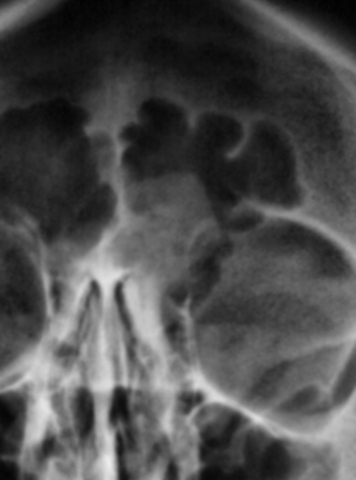

На рентгенограмме американского мужчины с жалобами на головную боль в лобной пазухе справа (если буква L означает лево) усматриваю гомогенное мягкотканное образование ~ 3х3см, расположенное пристеночно (по-видимому на передней стенке), прилежащее к медиальной, латеральной и нижней стенкам, с чётким дугообразно-ломаным верхним контуром. Состояние нижней стенки неясно (может быть полезна томограмма в 2х проекциях). Можно предположить периостальное наслоение.

В остальном всё спокойно, имеются лишь дополнительные бухты в лобной и гайморовой пазухах справа.

Но для начала пару замечаний. Во-первых, это конечно не остеома; остеома должна иметь плотность костной ткани при рентгенографии, в нашем случае плотность явно уступает окружающим костным структурам. Как верно было подмечено, образование исходящее из верхних этмоидальных камер распространяющиеся на фронтальную пазуху; верхний свободный контур выпуклый. Образование имеет "масс эффект" (expandile pattern of growth), и как бы оттесняет lamina papryceae и медиальную стенку орбиты. Такие признаки типичны для ПОЛИПОВ. Указанные уважаемым Валентином Львовичем стрелками стенки синусов; является гипертрофией полостей параназальных синусов, или гиперпневматизацией (не знаю какой термин используется в русской литературе). Такая находка является вариантом анатомического строения; хотя в старых монографиях можно встретит ассоциации такой находки с опухолями; гипертиреозом и т.д.

Пациента взяли на эндоскопическое оперативное вмешательство на основании моего заключения, проигнорировав рекомендацию провести КТ, которое позволяет более точно определить распространение и анатомические особенности строения пара-назальных синусов. При эндоскопии образование удалили; заключение морфологов: полип.

Но для начала пару замечаний. Во-первых, это конечно не остеома; остеома должна иметь плотность костной ткани при рентгенографии, в нашем случае плотность явно уступает окружающим костным структурам. Как верно было подмечено, образование исходящее из верхних этмоидальных камер распространяющиеся на фронтальную пазуху; верхний свободный контур выпуклый. Образование имеет "масс эффект" (expandile pattern of growth), и как бы оттесняет lamina papryceae и медиальную стенку орбиты. Такие признаки типичны для ПОЛИПОВ. Указанные уважаемым Валентином Львовичем стрелками стенки синусов; является гипертрофией полостей параназальных синусов, или гиперпневматизацией (не знаю какой термин используется в русской литературе). Такая находка является вариантом анатомического строения; хотя в старых монографиях можно встретит ассоциации такой находки с опухолями; гипертиреозом и т.д. Но обоснованного научного подтверждения нет; поэтому расценивается как вариант анатомического строения.